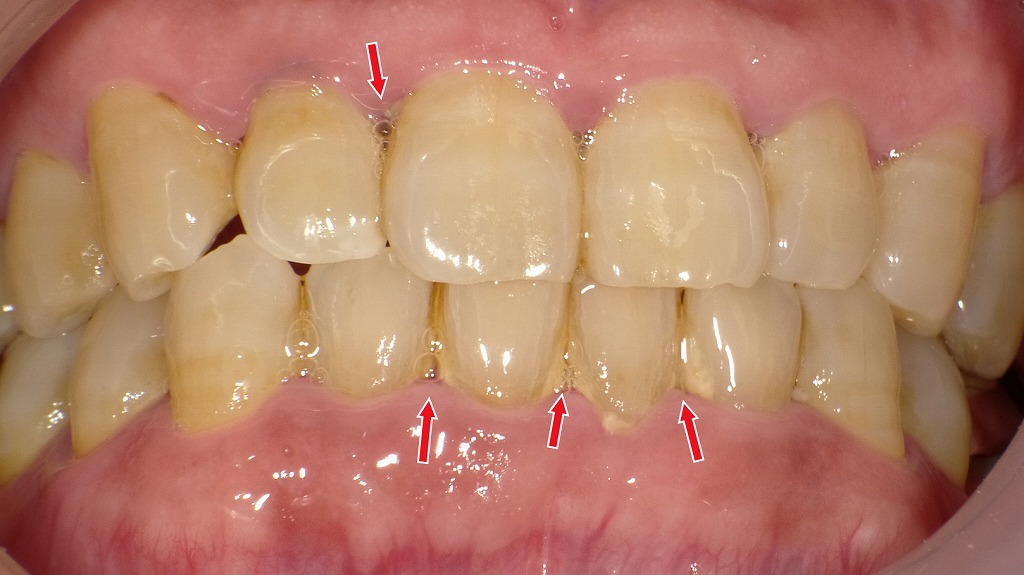

赤矢印部には硬く固着した歯石と歯肉の強い炎症が認められます。歯石が長期間放置されると、歯周ポケットが深くなり、歯を支える骨が徐々に失われ、最終的には“歯の喪失”につながります。早期のクリーニングと歯周治療が、歯を残すために不可欠です。